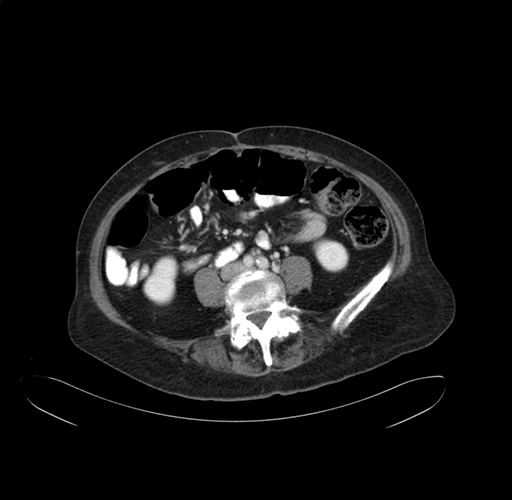

Axial Venous